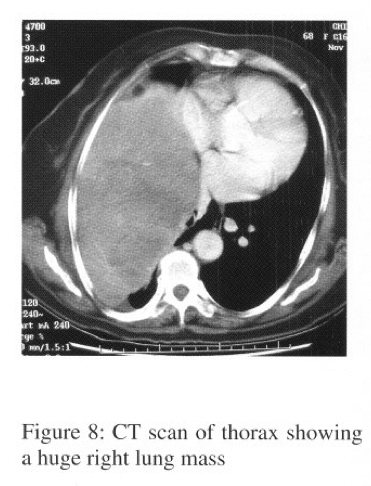

Arterial blood gases showed type I respiratory failure (pH7.44,PaC02 5.52,Pa02 7.30, HC03 27.2, Sa02 89%). Bronchoscopy showed a bulge seen over posterior segment of right upper lobe bronchus. Bronchial aspirate showed atypical cells. Transbronchial needle aspiration (TBNA) over right upper lobe bronchus was negative for malignancy. CT scan of thorax showed huge right lobulated lung mass with heterogeneous intra-lesional contrast enhancement and significant mass effect with displacement of the mediastinum towards left side and collapsed right upper, middle and lower lobes. Right sided pleural effusion was also present (Figure 4). The radiological feature was suggestive of mesothelioma, with differential diagnosis included other sarcoma.

SFT appears as a sharply delineated, sometimes lobulated mass with same density as the musculature on CT scanning with usua1ly homogeneous contrast enhancement due to rich vascularization. However non-enhancing areas can be seen due to tissue necrosis, myxoid degeneration, or haemorrhage within the tumour. Contact with the pleural surface and displacement or invasion of the adjacent structure are the characteristic features of SFT on CT scan. MRI study defines the extent of SFT more clearly when compared with CT scanning and provides better tissue characterization. Both benign and malignant SFT have low signal intensity on TI -weighted images; while on T2-weighted images, benign SFT has a low intensity whereas malignant SFT appears with high signal intensity (due to increased vascularity, oedema and ce1lularity).